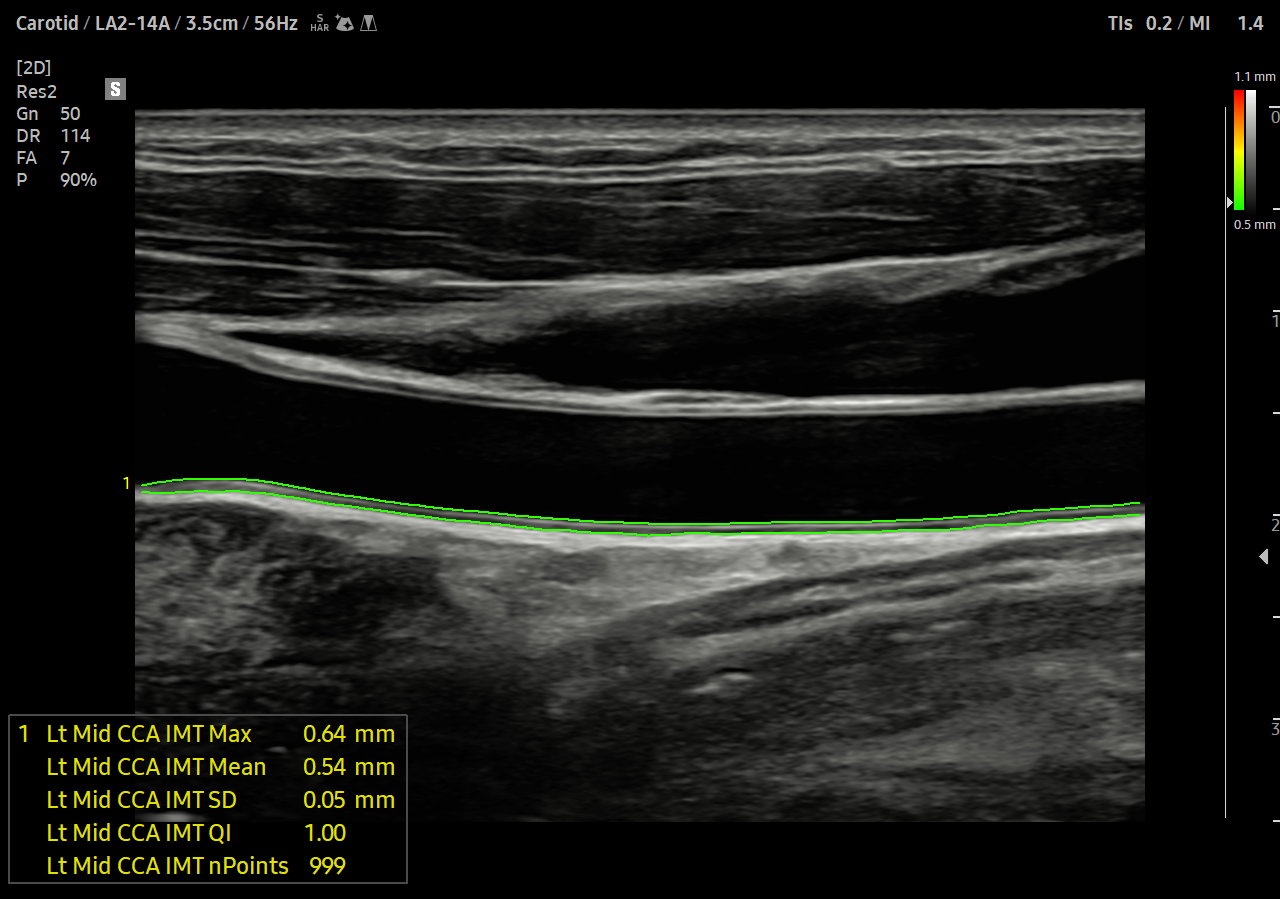

Sistemul ArterialAnalysis detectează modificările funcționale ale vaselor, furnizând valori de măsurare precum rigiditatea, grosimea intimă-media și pulsul de viteză comun. artera carotida. Deoarece schimbările funcționale apar înaintea modificărilor morfologice, această tehnologie sprijină diagnosticarea precoce a bolilor cardiovasculare.